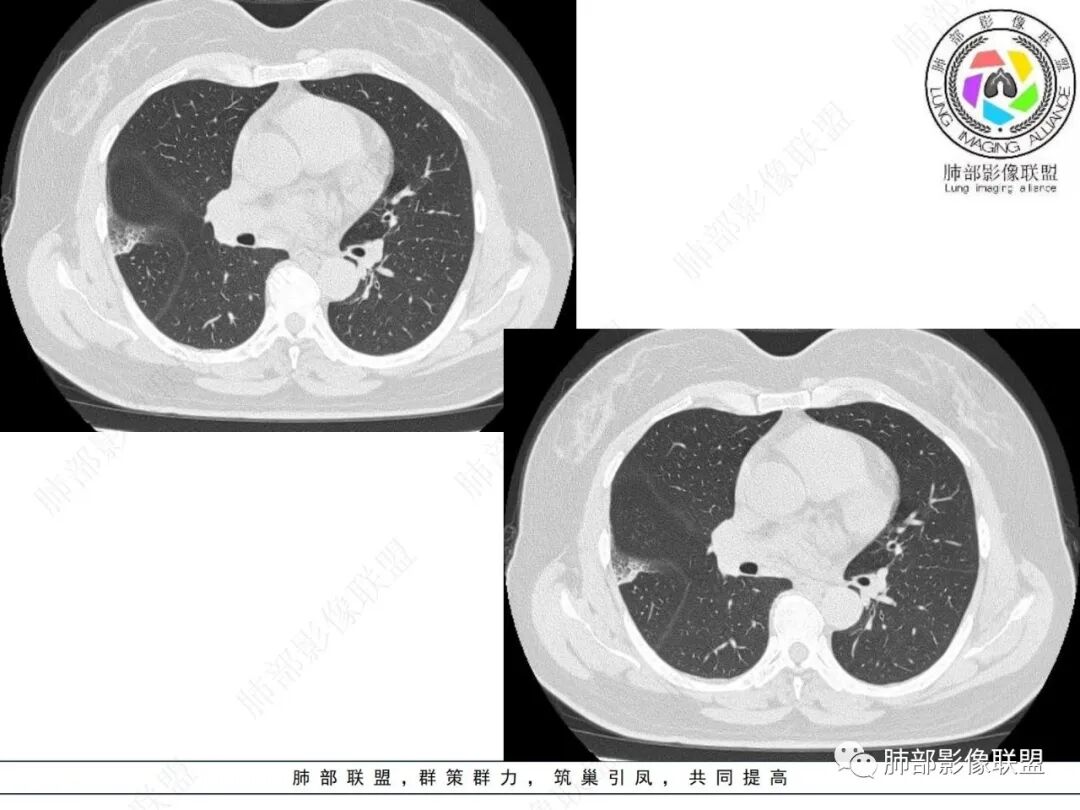

2.影像特点:

右肺上叶胸膜下混合磨玻璃团片影。

周围磨玻璃部分间杂条索状高密度区,密度欠均匀(可疑重力分布趋势),其磨玻璃影边界大多较清楚或可分辨,部分“L型”边缘,提示小叶间隔阻挡可能。血管穿行自如,可疑远端支气管进入。

实性部分较密实,不规则,隐约见棘突或刺状突起,未见钙化、空洞或液化区,实性边缘可见斑状略低密度间隙(借用王兆宇老师课件,称其呈“松软”的形态)。动脉期实性部分较明显不均匀强化,如果有完整增强图,还可以观察内部血管情况。

纵隔窗相对肺窗病灶相对小,仅部分实性影呈现。病灶张力不高,相邻胸膜增厚(糊墙),未见明显胸膜牵拉凹陷。

未见卫星病灶,远处未见磨玻璃结节影。

双肺门及纵隔未见明显增大淋巴结。心包及胸腔未见积液。